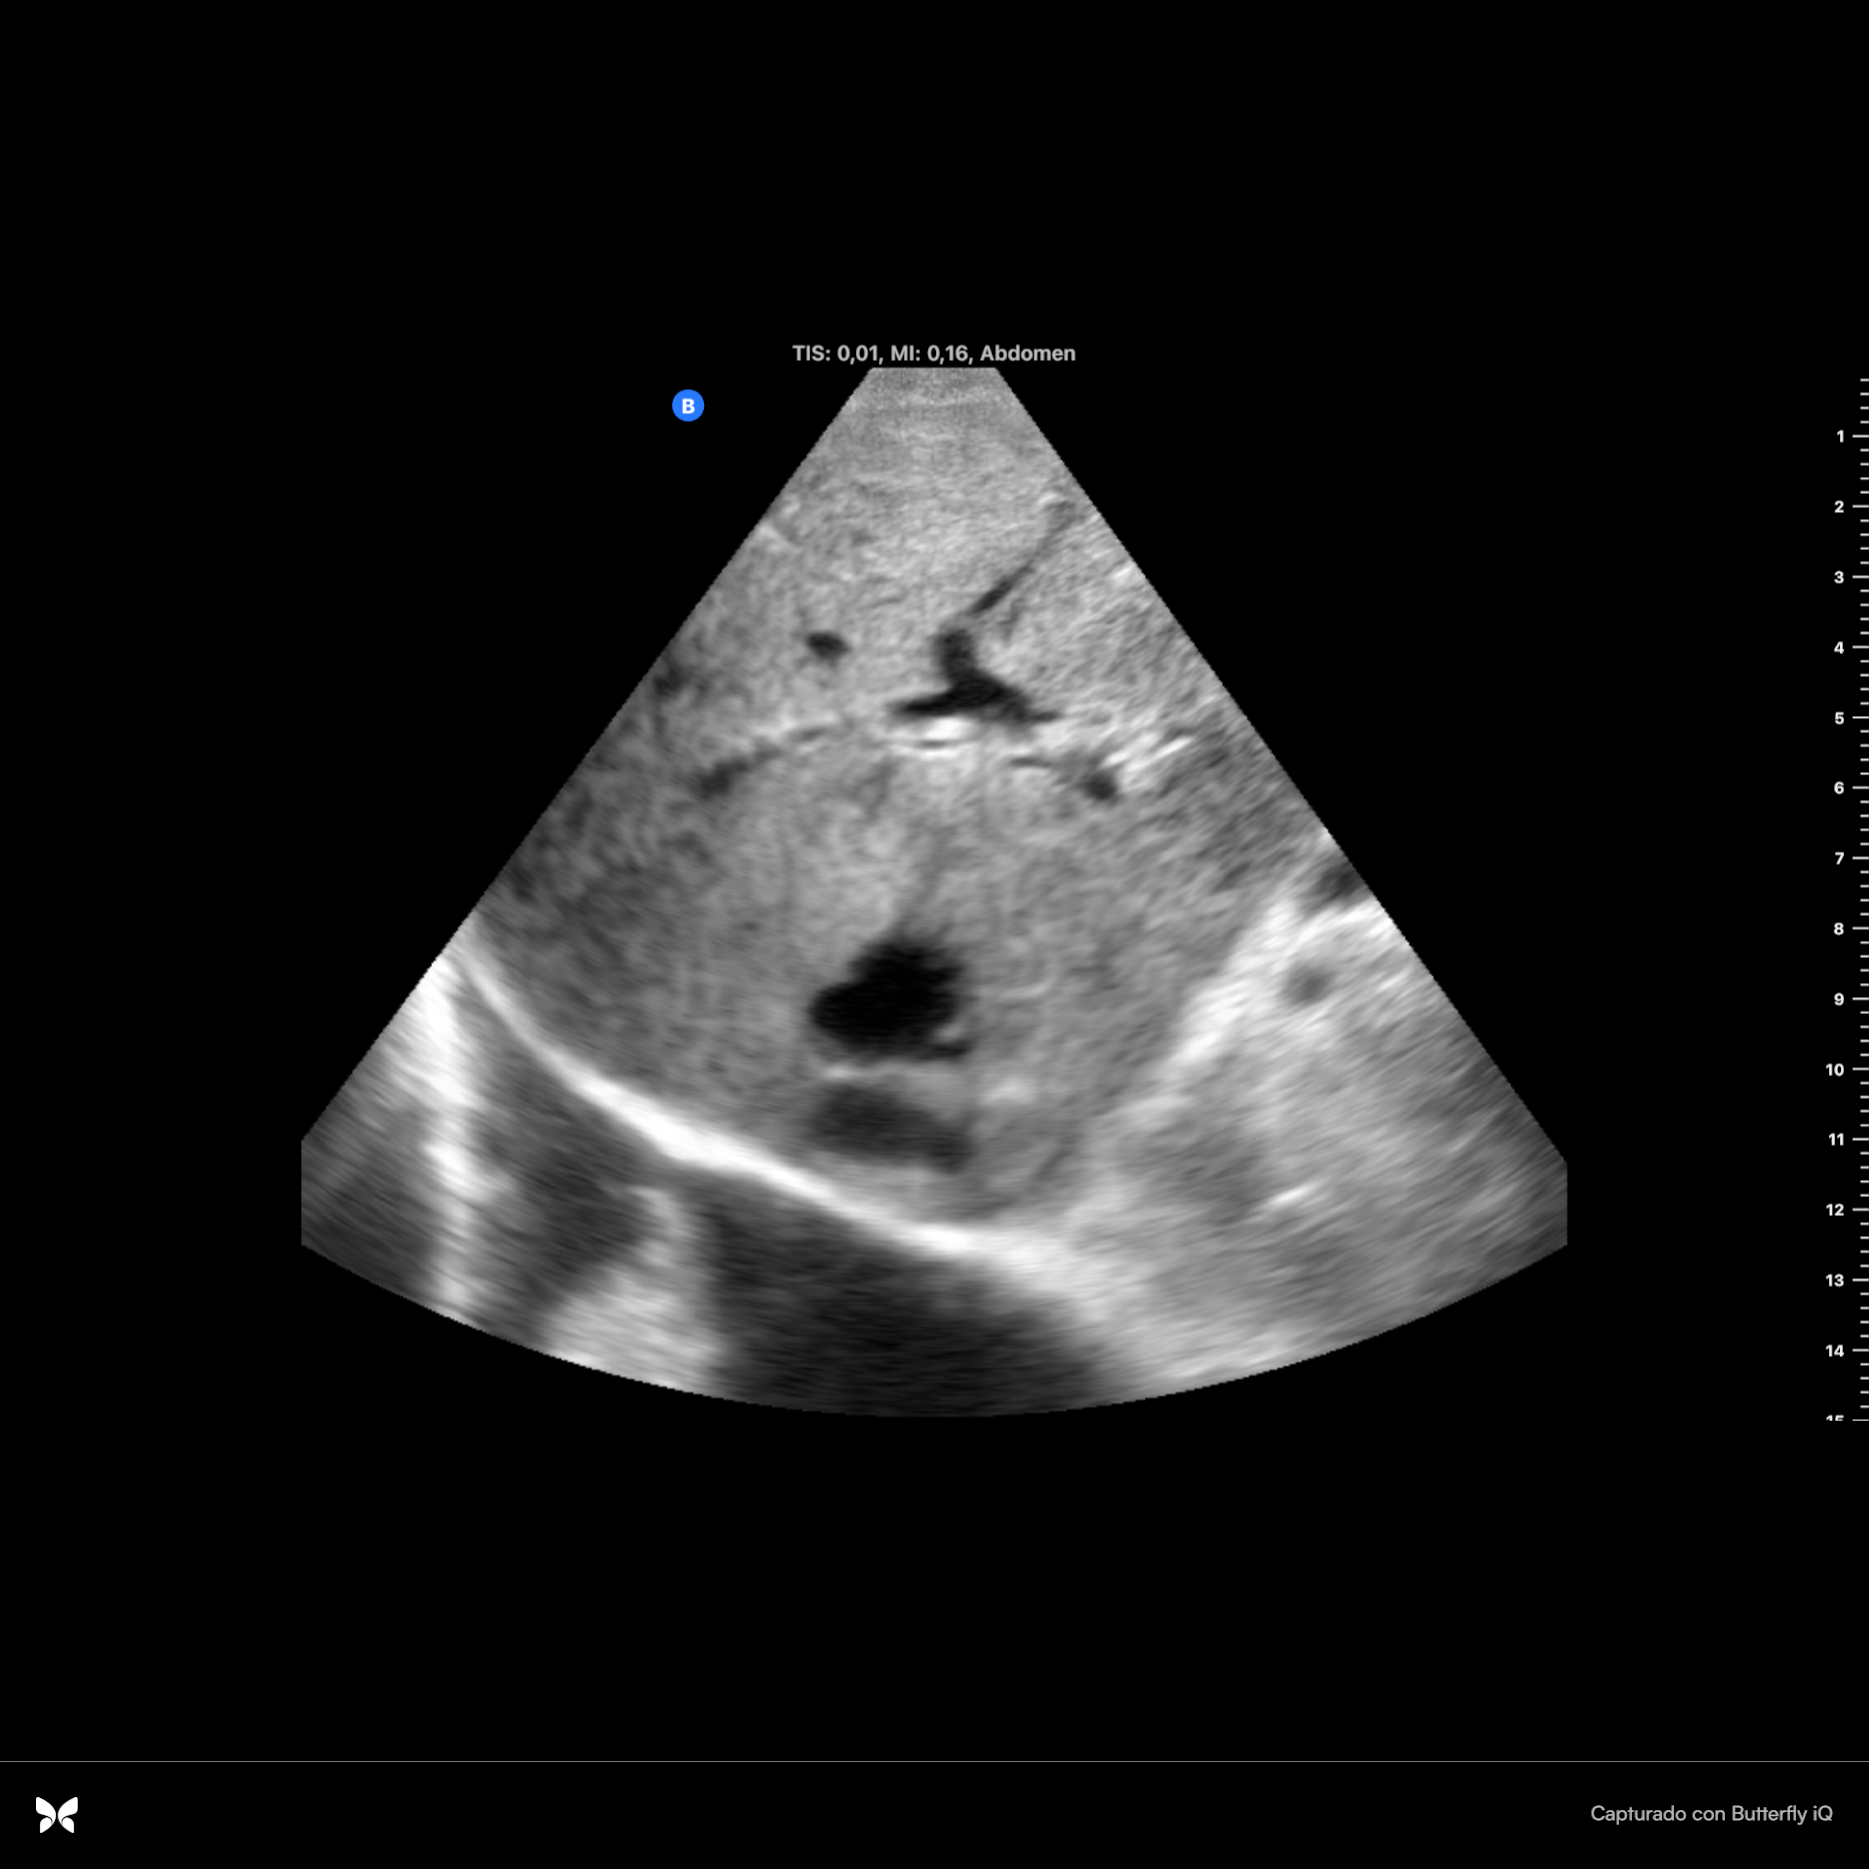

Se observan dos imágenes hiperecoicas en infundíbulo de vesícula que dejan sombra acústica posterior, una de ellas de 2 cm x 0.94 cm con aumento de grosor de vasos suprahepáticas. Parénquima hepático sin alteraciones. Se observa espacio anecoico superior al diafragma. Resto sin hallazgos.

En ecografía hospitalaria se observa claramente la dilatación de vía intra y extrahepática: colédoco con calibre de hasta 18 mm. Además se describen más hallazgos de insuficiencia cardíaca tales como líquido perivesicular y derrame plural derecho de espesor de hasta 7.5 cm y atelectasia del parénquima pulmonar.